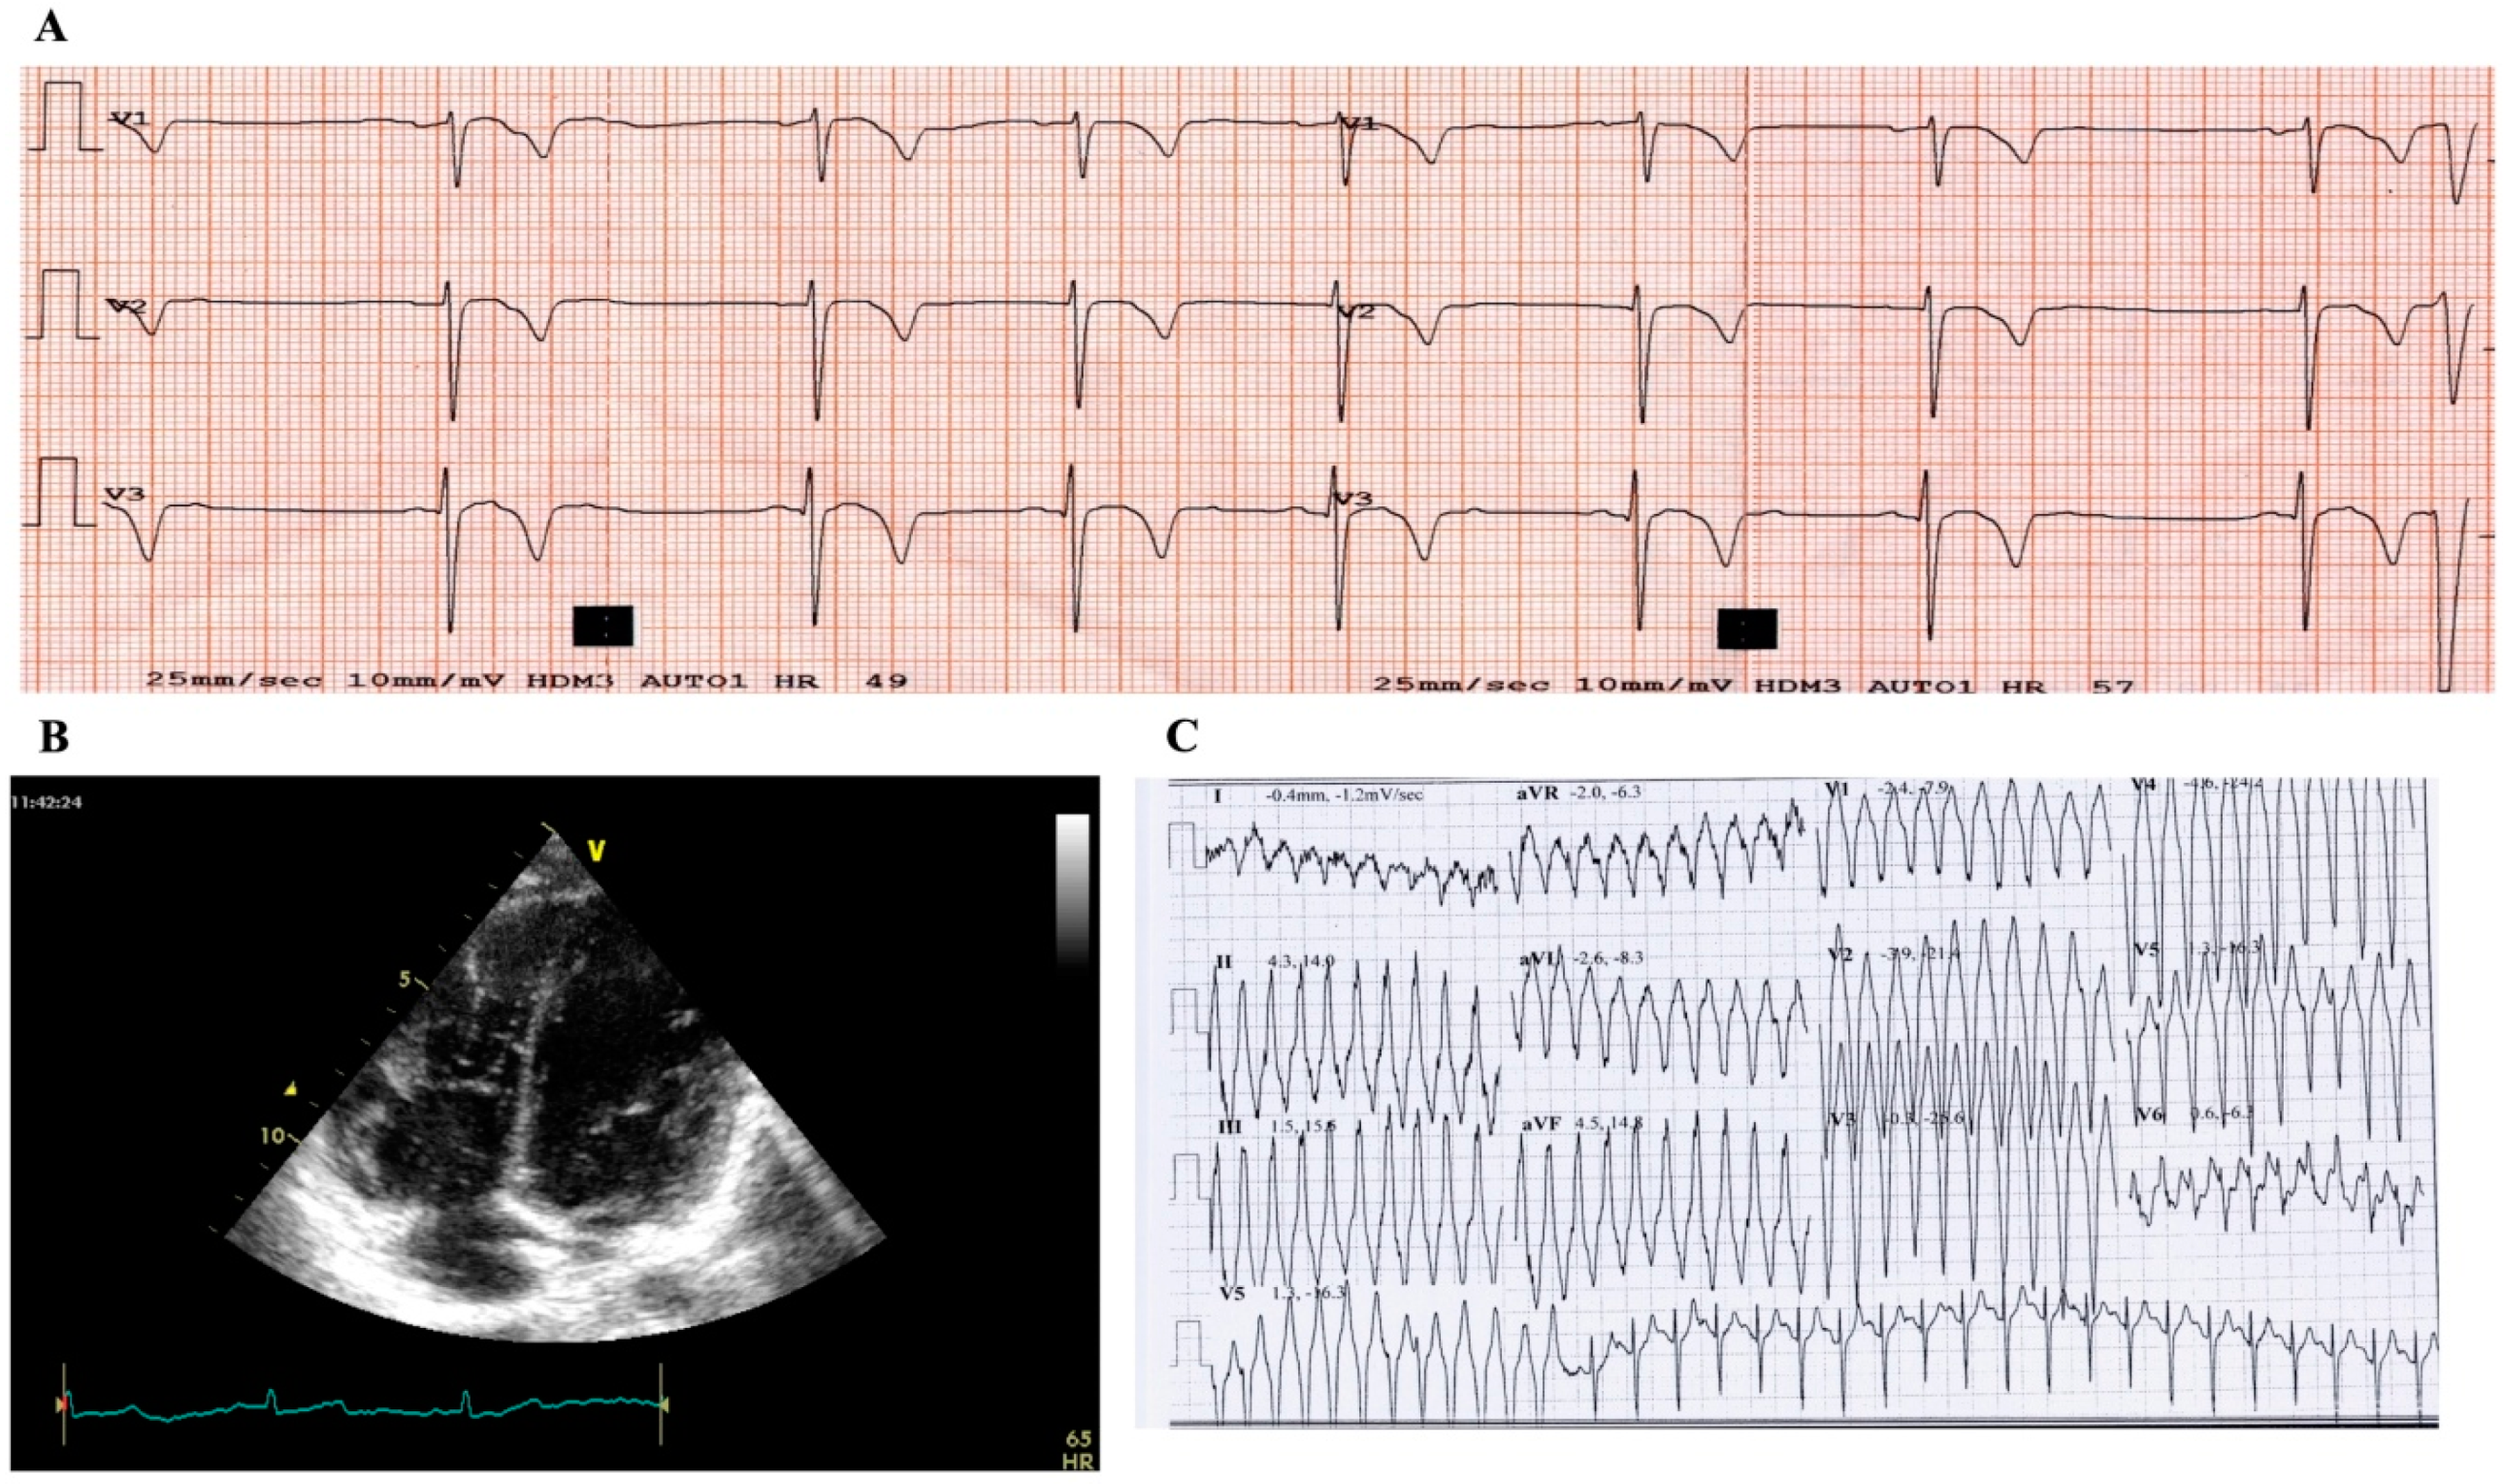

2.1. Case Study Presentation and Clinical Description

2.2. Case Study: Clinical Molecular Biology Investigation